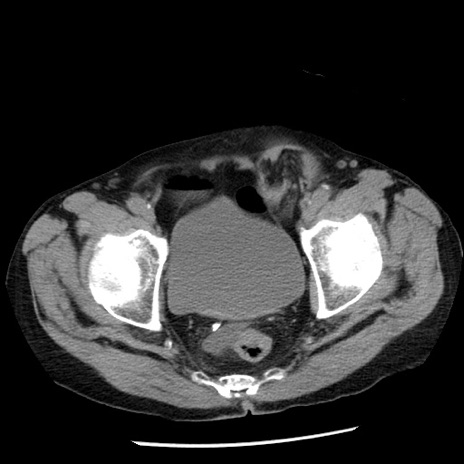

症例26(横断像)

【症例】80歳代男性

【主訴】嘔吐

【現病歴】昨晩2回嘔吐あり、今朝になっても嘔吐あり。来院。

【既往歴】胃潰瘍

【身体所見】意識清明、BT 37.6℃、BP 166/95mmHg、HR 100bpm、SpO2 97%、腹部:平坦・軟、腸蠕動音聴取良好、圧痛なし。

【データ】WBC 21900、CRP 1.46